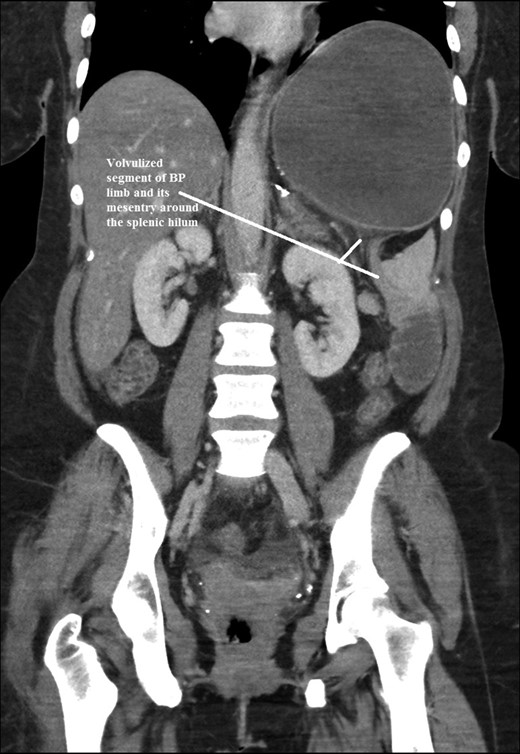

The intraoperative findings were not consistent with the radiological findings (Figs 1–4). As shown in the CT scan of abdomen and pelvis; multiple loops of dilated small bowel were seen, more predominantly dilated and matted bowel complex just above the spleen. The dilated bowel complex was decompressed using needle aspiration to help reduction of the bowel loops. The ileo cecal junction was then identified and traced back to the perisplenic hilar region. The trifurcation of three bowel loops (Roux limb, biliopancreatic limb and common limb) were identified with identification of ligament of Treitz. The prior gastric bypass was of ante colic- ante gastric type and Peterson’s defect was not closed. The above described bowel trifurcation had sunken postero- inferior to the spleen and had herniated through a potential space underneath the spleen and torsed around the splenic vessels and hilum. This picture was consistent with perisplenic small bowel volvulus. As noted earlier there was a massively dilated proximal small bowel segment above the spleen, displacing it caudally. Careful adhesiolysis was performed inferior to the spleen to release the segment of the trifurcation. The bowel segments once reduced were assessed and appeared viable. Of note, the spleen appeared better perfused after reduction. The remnant hernia defect of size 2 × 3 × 2.5 cm around the hilar region was then approximated using interrupted non-absorbable sutures. Enterotomy at the decompression site was closed with non absorbable suture. All potential sites of IH were re-examined and there was no evidence of any other internal herniation. Coelomic cavity was thoroughly irrigated and operation concluded successfully. Postoperative hospital stay was uneventful, and the patient was discharged home after two days.

Coronal CT scan of abdomen and pelvis showing volvulized bilio- pancreatic and Roux limbs within the obstructed segments in the splenic hilar region.

Coronal CT scan of abdomen and pelvis showing Volvulized segment of bilio-pancreatic limb and its mesentery in the spleen hilum.